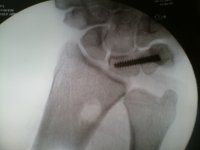

Kelly's Fusion Surgery

Fusion Hardware Fusion Surgery

Fusion Plate Top View